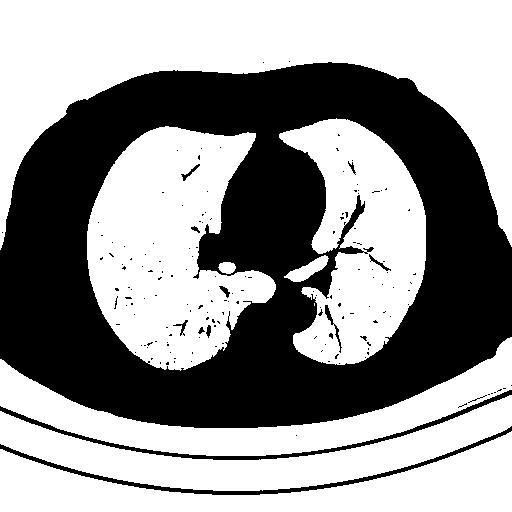

Unsegmented lung (input):

unsegmented lung